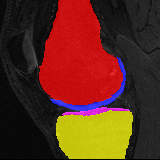

Knee MRI experiment: We test our method on 3D knee MRIs from the Osteoarthritis Initiative (OAI) 111https://nda.nih.gov/oai/ and corresponding segmentations of femur and tibia as well as femoral and tibial cartilage [1]. From a total of 507 labeled images, we use 200 for training, 53 for validation, and 254 for testing. To test registration performance we use 10,000 random image pairs from the test set. All images are affinely registered to an atlas built from the training images, resampled to isotropic spacing of 1mm, cropped to and intensity normalized to [0,1]. In addition, right knee images are flipped to be consistent with left knees. For training, the loss weights are , , and based on approximate hyper-parameter tuning. Note that when computing from the displacements, the image coordinates are scaled to [-1, 1] for each dimension following the convention in the interpolation function of PyTorch.

Results: All trained networks are evaluated using Dice overlap scores between predictions and the manual segmentations for the segmentation network, or between the warped moving segmentations and the target segmentations for the registration network. Tabs. 1 and 2 show results for the knee and brain MRI experiments respectively in Dice scores (%). Fig. 2 shows examples of knee MRI registrations and brain MRI segmentations.

Knee results: On knee MRIs, our method improves segmentation scores over separately learned networks by about 1.2 and 0.5, and registration scores increase by about 3.1 and 3.0, when training with 5 and 10 manual segmentation respectively. Especially for the challenging cartilage structures, our joint learning boosts segmentation by 1.4 and 0.7, and registration by 5.5 and 5.2 for N=5 and N=10 respectively.

Qualitative results: DA achieves more anatomically consistent registrations than the mono-networks on the knee (Fig. 2) and Brain MRI samples (see supplementary material).